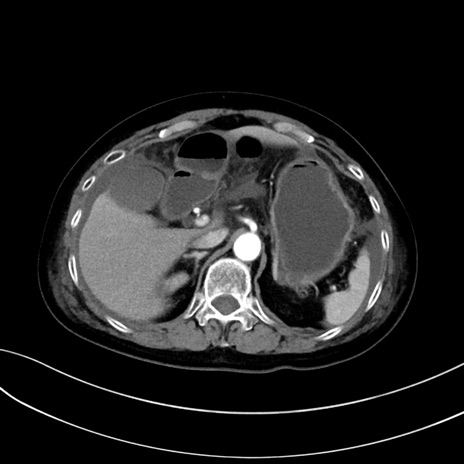

症例13 CT(横断像)1日半後